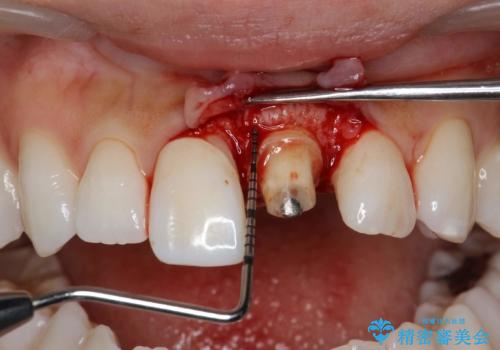

今回は、仮歯の状態で歯の長さを調整する歯周外科をおこなう

→歯茎の治りを待っている間、根管治療のやり直しを行う

→土台を築造しセラミックを完成させる

ことで前歯を残し、長さが揃うようにしました。

左上の前歯がわずかに短いことを気にされていたため、歯周外科にてこれを可及的に改善し、セラミックにて修復を行いました。